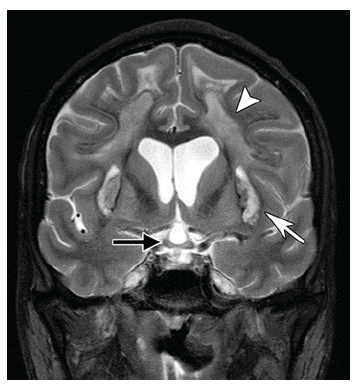

En la campimetría, la pérdida visual central fue el defecto más frecuente y todos los pacientes del estudio de Arabia Saudí desarrollaron atrofia óptica 21. 13 de los 50 pacientes de dicha serie presentaron temblores o temblor con rigidez y, en la resonancia magnética (RM) cerebral de 30 pacientes, se encontró disminución del calibre del nervio óptico bilateral, 11 con necrosis del putamen y, ocasionalmente, del claustrum bilateral, además de 2 pacientes con focos de desmielinización subcortical y de sustancia blanca profunda 21. La variabilidad de la dosis de metanol relacionada con daño neurológico se puede deber a susceptibilidad individual, consumo de etanol concomitante y sesgo de memoria sobre la cantidad ingerida 20-21. La selectividad tóxica del metanol sobre el nervio óptico está en relación con la inhibición de la actividad del citocromo oxidasa, por el ácido fórmico que previene la fosforilación oxidativa mitocondrial. Estudios histopatológicos en animales mostraron daño laminar y retrolaminar del nervio óptico con disrupción del flujo axonal, edema y agrupamiento mitocondrial, fragmentación de neurofilamentos y neurotúbulos, vacuolas axonales y cambios en la glía 21.

La lesión cerebral más común por IM es la necrosis hemorrágica o no hemorrágica bilateral del putamen 21. La causa de la vulnerabilidad de los ganglios basales al metanol se desconoce, pero puede deberse a una mayor concentración de ácido fórmico, al flujo sanguíneo, la sensibilidad aumentada a metabolitos del metanol o a su mayor capacidad de apoptosis 21; sin embargo, en estudios de RM en pacientes con IM, se han encontrado lesiones subcorticales y de la sustancia blanca profunda, lesiones corticales cerebrales y cerebelosas, lesiones del mesencéfalo, hemorragias cerebrales e intraventriculares, edema cerebral y realce parcial de las lesiones necróticas 22 . Aunque el compromiso visual y los síndromes extrapiramidales son los más frecuentemente asociados a la IM, el espectro de presentación es grande e incluye: coma, crisis epilépticas, delirio, ataxia y síndromes cognitivos en relación con la extensión de la lesión, más allá de los ganglios basales 23.

Las neuroimágenes juegan un papel primordial en la identificación de neurotoxicidad por metanol. Las lesiones aparecen en los ganglios basales, especialmente en el putamen, debido a la sensibilidad específica de sus células, sin embargo, las lesiones se pueden extender a las fibras de la sustancia blanca y, en ocasiones, ampliando los diagnósticos diferenciales 25-29 (figura 4).

La necrosis hemorrágica del putamen es el hallazgo más característico, con grados variables de necrosis del nervio óptico. La necrosis hemorrágica se presenta con hiperatenuación en la tomografía computada, señales hiperintensas en las secuencias T2 de RM y como focos de hipointensidad en las secuencias de eco de gradiente y susceptibilidad 28-29. En las imágenes de espectroscopía por RM, se puede encontrar reducción del N-acetil-aspartato y elevación del lactato. En ocasiones, también es posible observar lesiones en la médula espinal (figura 5).